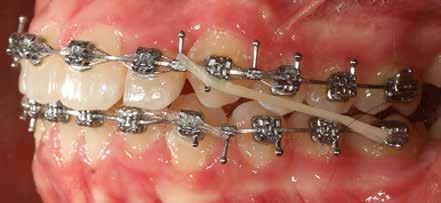

A Pitts21-es fix készülékes kezelés során a harapásemelőket a felső nagyőrlő fogakra ragasztottuk, hogy a felső molárisok intrúziójával segítsék a harapás zárását (8. kép) Ún. keresztharapásos, majd később normál class 2-es gumihúzással (9–10. képek), továbbá az elülső fogakon alkalmazott ún. Rainbow harapás-záró gumihúzással (11. kép) korrigáltuk a jobb oldali teljes premolárisnyi distal-harapást, valamint az elülső nyitott harapást.

6 hónap után a nyitott harapás már nagyjából összezárásra került (12. kép)! A gumihordás a kezelés teljes hosszában folyamatos, éjjel-nappal, 22-24 órában az étkezések és az utánuk történő fogmosás kivételével.